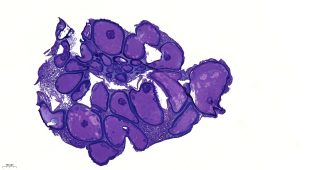

Tanulmányuk két különböző halfajból származó esetet mutat be, amelyeknél stresszhez köthető, krónikus LCDV-fertőzést figyeltek meg. A halak mell-, farok- és hátúszóján megjelenő, szabad szemmel is látható, jellegzetes lymphocystis-csomók alakultak ki. Az élő állatokról kaparékmintavétellel gyűjtött elváltozásokat fény- és elektronmikroszkópos vizsgálatoknak vetették alá.

A morfológiai elemzés során részletes megfigyeléseket tettek a vírus feltételezett replikációjáról a lymphocystis-csomók citoplazmatikus zárványtesteiben.